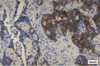

Islet Cell Tumors